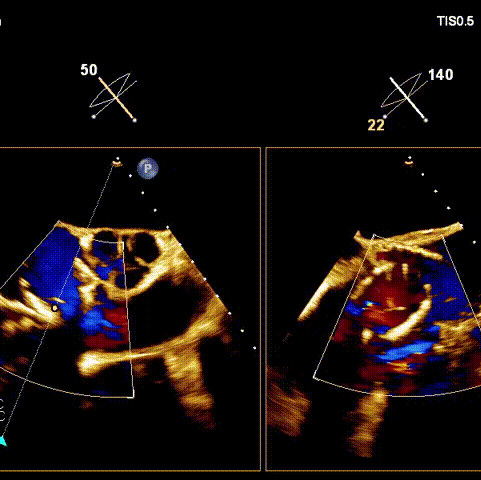

術后超聲

術前經過全面系統的評估后,考慮患者存在高齡、心功能減低、三尖瓣瓣環重度擴張(三尖瓣極重度反流)等高危因素,因此廈心結構心團隊聯合超聲心動、麻醉及護理團隊,制定了詳盡的圍術期治療方案及術中治療難點預案。術中,由王焱院長主刀,在蘇茂龍主任超聲心動團隊的輔助,上海市第一人民醫院陸方林主任的協助下,僅用時30分鐘,即順利完成了三尖瓣原位置換的手術。術中患者血流動力學穩定,術后即刻顯示LuX-Valve Plus瓣膜位置良好,固定穩定,瓣膜功能正常,無瓣周漏。

觀摩手術的臺灣專家對此次手術過程及LuX-Valve Plus器械展示出的優異性能表示贊譽,表示與傳統外科三尖瓣治療方式相比,LuX-Valve Plus介入三尖瓣治療創傷小,安全性高,手術時間短,術中術后患者血流動力學可平穩過渡;且與現有的三尖瓣緣對緣修復手術相比,LuX-Valve Plus原位三尖瓣置換對術中影像依賴度相對更低,操作更加便捷,并且憑借獨特的錨定及瓣葉固定方式可以最大程度的避免高度房室傳導阻滯的發生,同時也擁有較為豐富的產品規格,可以適應不同三尖瓣瓣環擴張程度的患者,自適應防漏環還可以有效預防瓣周漏的發生,產品的諸多特點讓與會專家再次對國產原創醫療器械刮目相看,并期望可以早日引入海峽對岸,讓臺灣地區的患者也可以使用到祖國的原創器械,救治更多的患者。